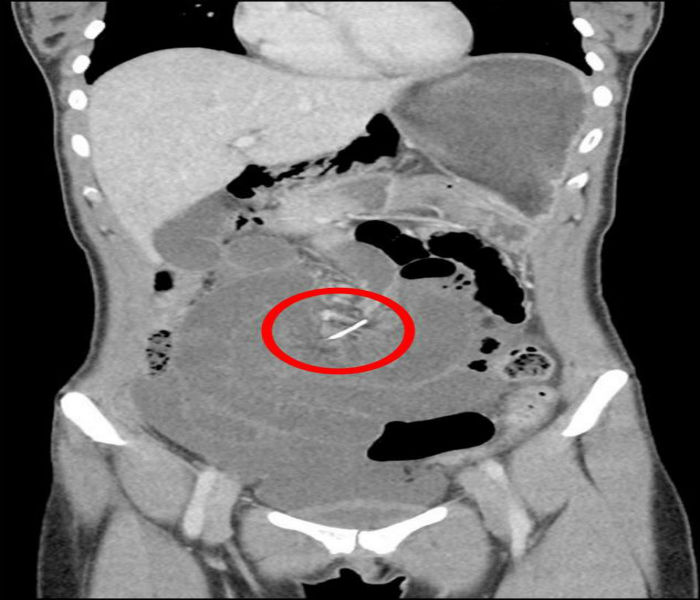

ਆਸਟ੍ਰੇਲੀਆ— ਕਈ ਵਾਰ ਅਸੀਂ ਪੇਟ ਦਰਦ ਨੂੰ ਅਣਗੋਲਿਆ ਕਰ ਜਾਂਦੇ ਹਾਂ।, ਜਿਸ ਕਾਰਨ ਇਹ ਸਾਡੇ ਲਈ ਵੱਡੀ ਪਰੇਸ਼ਾਨੀ ਬਣ ਜਾਂਦੀ ਹੈ। ਪੱਛਮੀ ਆਸਟ੍ਰੇਲੀਆ 'ਚ ਰਹਿਣ ਵਾਲੀ ਇਕ ਔਰਤ ਨਾਲ ਵੀ ਅਜਿਹਾ ਹੀ ਹੋਇਆ। 30 ਸਾਲਾ ਔਰਤ ਦੇ ਪੇਟ 'ਚ ਜਦੋਂ ਦਰਦ ਬਰਦਾਸ਼ਤ ਤੋਂ ਬਾਹਰ ਹੋ ਗਿਆ ਤਾਂ ਉਹ ਹਸਪਤਾਲ ਪਹੁੰਚੀ। ਪੱਛਮੀ ਆਸਟ੍ਰੇਲੀਆ ਸਥਿਤ ਹਸਪਤਾਲ ਦੇ ਐਮਰਜੈਂਸੀ ਵਾਰਡ 'ਚ ਔਰਤ ਨੂੰ ਦਾਖਲ ਕੀਤਾ ਗਿਆ। ਡਾਕਟਰ ਨੇ ਜਦੋਂ ਉਸ ਦਾ ਚੈਕਅਪ ਕੀਤਾ ਤਾਂ ਉਨ੍ਹਾਂ ਨੂੰ ਲੱਗਾ ਕਿ ਸ਼ਾਇਦ ਪੇਟ ਵਿਚ ਪੱਥਰੀ ਹੋਵੇਗੀ ਪਰ ਸੀਟੀ ਸਕੈਨ 'ਚ ਕੁਝ ਹੋਰ ਹੀ ਸੱਚਾਈ ਸਾਹਮਣੇ ਆਈ।

ਸਕੈਨ ਦੀ ਰਿਪੋਰਟ 'ਚ ਔਰਤ ਦੇ ਪੇਟ ਵਿਚੋਂ 7 ਸੈਂਟੀਮੀਟਰ ਧਾਤੂ ਦੀ ਤਾਰ ਦਾ ਟੁੱਕੜਾ ਮਿਲਿਆ। ਇਸ ਤੋਂ ਬਾਅਦ ਡਾਕਟਰਾਂ ਨੇ ਤੁਰੰਤ ਆਪਰੇਸ਼ਨ ਕਰ ਕੇ ਉਸ ਤਾਰ ਦੇ ਟੁੱਕੜੇ ਨੂੰ ਬਾਹਰ ਕੱਢਿਆ। ਡਾਕਟਰਾਂ ਦਾ ਕਹਿਣਾ ਹੈ ਕਿ ਔਰਤ ਕਈ ਸਾਲਾਂ ਤੋਂ ਦੰਦਾਂ ਵਿਚ ਤਾਰ ਲੱਗਾ ਰਹੀ ਸੀ ਪਰ 10 ਸਾਲ ਪਹਿਲਾਂ ਉਸ ਤਾਰ ਦੇ ਟੁੱਕੜੇ ਨੂੰ ਔਰਤ ਨੇ ਨਿਗਲ ਲਿਆ, ਜਿਸ ਕਾਰਨ ਉਸ ਦੀ ਅਜਿਹੀ ਹਾਲਤ ਹੋ ਗਈ। ਔਰਤ ਨੇ ਡਾਕਟਰ ਦਾ ਧੰਨਵਾਦ ਕੀਤਾ ਅਤੇ ਕਿਹਾ ਕਿ ਉਨ੍ਹਾਂ ਨੇ ਉਸ ਦੀ ਸਭ ਤੋਂ ਵੱਡੀ ਮੁਸ਼ਕਲ ਦਾ ਹੱਲ ਕੀਤਾ ਹੈ। ਡਾਕਟਰਾਂ ਨੇ ਕਿਹਾ ਕਿ ਔਰਤ ਹੁਣ ਪੂਰੀ ਤਰ੍ਹਾਂ ਸਿਹਤਮੰਦ ਹੈ।